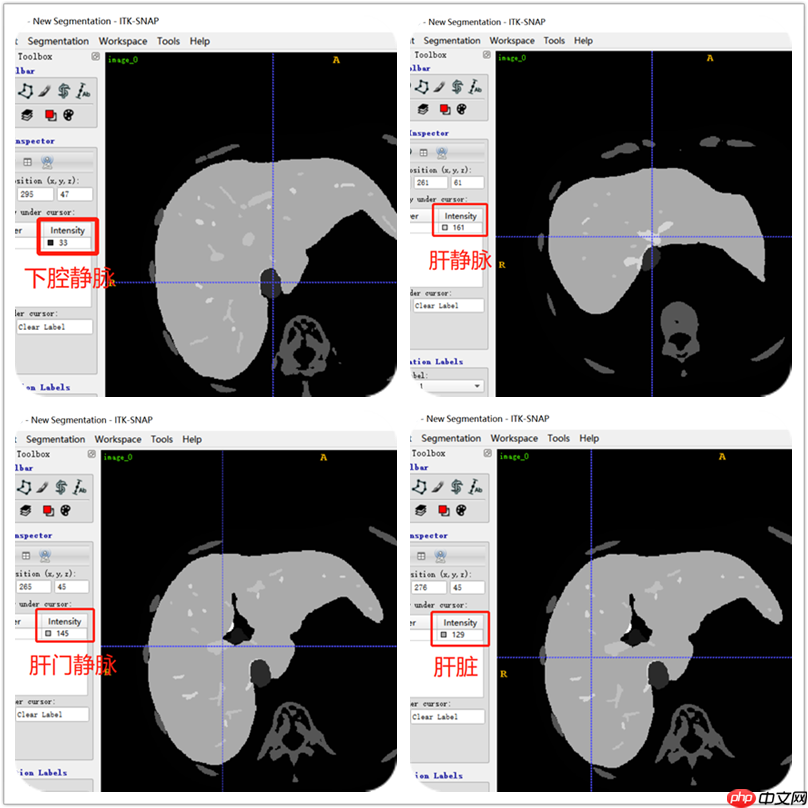

用ITK-SNAP软件查看label数据,可以看到肝脏、肝静脉、下腔静脉、肝门静脉的标签。从下图可以肝标签固定用了129数值,门静脉用了145数值,肝静脉用了161数值,下腔静脉用了33数值。根据这些数值就区分不同标签。不是全部label都是用相同的数值表示。所有要注意,不过肝静脉和肝门静脉的数值都包括这些:145,209,465,401,337,273,161,225,481,417,353,289。以下分割主要是针对肝静脉和肝门静脉。